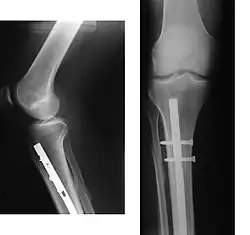

Рентгеновское исследование позволяет более точно установить вид перелома и положение отломков. Рентгенография — стандартный метод диагностики при подтверждении перелома. Именно наличие рентгеновского снимка повреждённого участка служит объективным подтверждением факта перелома. На снимке должны быть изображены два сустава, расположенные дистальней и проксимальней места поражения, кость должна быть изображена в двух проекциях, прямой и боковой. При соблюдении этих условий рентгеновское исследование будет адекватным и полноценным, а возможность ошибочной диагностики минимальна.[L 8]

На рентгенограмме изображён перелом большеберцовой кости, подвергшийся хирургическому лечению. 4 снимка в 2 проекциях. На первой паре снимков — верхняя треть голени и коленный сустав (сустав, расположенный проксимальней места перелома), на второй паре снимков — голеностопный сустав (сустав, расположенный дистальней места перелома). Большеберцовая кость фиксирована антероградно введённым в костно-мозговой канал гвоздём (UTN — unreamed tibial nail), блокированным 5 винтами. Такая конструкция позволяет фиксировать отломки и обеспечивает адекватную регенерацию. После формирования костной мозоли металлофиксатор удаляется.